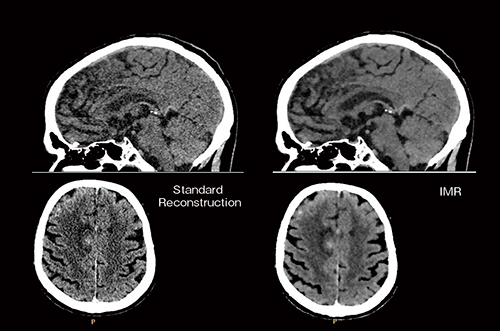

頭部単純CT撮影においては,非常に低いCT値差の検出が求められるため,画像ノイズを限りなく少なくする必要があることはよく知られている。そのため,従来のFBP法においてはスライス厚を厚くする,ほかの部位に比べ高い線量を必要とする,などの措置を講ずる必要があった。脳神経外科領域におけるIMRのクリニカルベネフィットは,Virtually Noise-Free Imagingによって,頭部単純CTにおいて目的に応じた任意のスライス厚を画像ノイズの影響を受けずに提供でき,かつ線量低減を図ることのできる可能性があることである(図2)。

図2 IMR臨床画像(頭部単純CT)